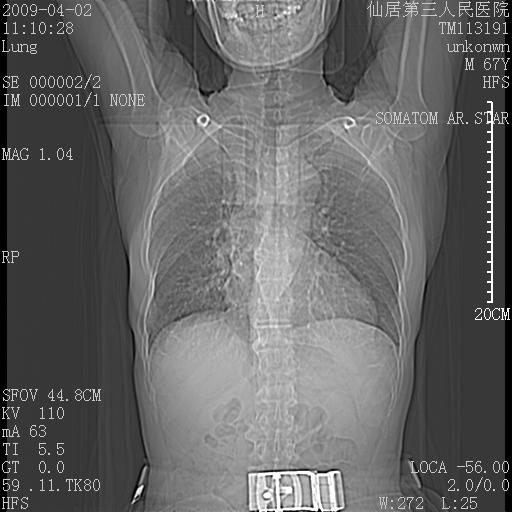

患者老年男性,乏力畏寒来诊,摄胸片示右下肺感染性病变,抗炎两周后复查胸片,无好转有进展。

后做ct平扫表现如下: